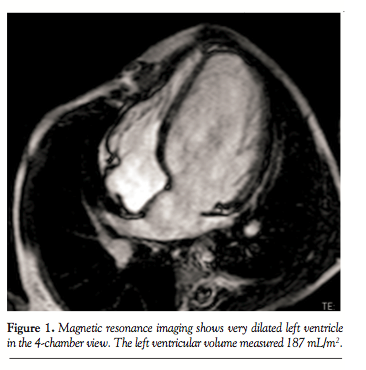

second heart sound. Echocardiogram showed a hugely dilated left ventricle (LV) of unknown cause (LV end-diastolic diameter of 60 mm; z-score, +8). There was mild tricuspid regurgitation with Doppler-derived gradient of 60 mm Hg. Imaging of the branch PAs and the arch was very difficult; hence, the patient was referred for MRI scan to investigate the unusual clinical and echocardiographic findings. Cardiac MRI confirmed severe LV dilation, with end-diastolic volume of 187 mL/m2 (Figure 1) and continuous flow in the left PA throughout systole and diastole, as detected with the phase-contrast flows taken in the left PA (Figure 2). Although the left PA appeared severely stenosed, the stroke volume to both PAs (differential flow) was equal. In addition, the cumulative flow to the PAs was double that of the flow in the main PA, implying that an additional source of flow beyond the PA bifurcation was present. The possibility of an iatrogenic aortopulmonary window was raised and the patient was taken to the catheterization laboratory in order to

His medication was discontinued. His clinical progress was excellent and he started gaining weight. Cardiac MRI 14 months after the percutaneous procedure showed significant reduction of the LV dimensions from 187 to 117 mL/m2 (Figure 6). In addition, the left PA was widely patient and the flow pattern in it had now normalized and was no longer biphasic. The patient remains well and medication free 2 years after the procedure.

deterioration of the patient with severe LV dilation, pointed to the immediate development of the aortopulmonary window in the catheterization laboratory. This went unnoticed until his family noted a visually prominent cardiac impulse and severe LV dilation was found on echocardiogram. That finding, along with the continuous murmur on auscultation, pointed immediately to a left-to-right shunt. However, the echocardiogram, as is often the case for these patients, provided very poor-quality images of the great vessels. The cardiac MRI was therefore essential in order to delineate the anatomy and point toward the cause of the LV dilation. The MRI hint that pointed us to the diagnosis was the continuous flow in the left PA pattern as observed on the phase contrast images (Figure 2), along with the cumulative flow to the branch PAs, which was double that of the main PA, indicating an additional source of flow to the lungs. The suspicion was confirmed with cardiac catheterization and the window was sealed off with a covered stent.